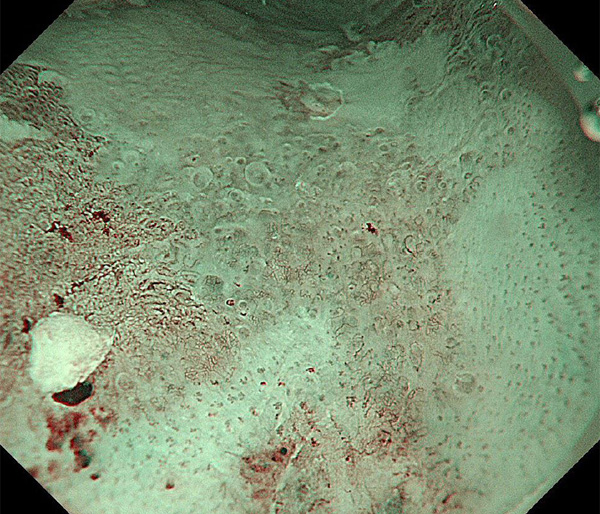

内視鏡所見と病理組織像の1対1対応が可能な症例を公募いたします。主にLSBEに発生した早期癌(HGDを含む)を対象としますが、興味深い症例であればSSBE癌でも結構です。採否は世話人へご一任ください。

特に、本邦では極めて稀なlong segment Barrett’s esophagus(LSBE)から発生した早期癌は、診断に難渋する場合も多く、欧米ではランダム生検による検出が標準的とされています。背景のBarrett食道もろとも全体を内視鏡切除+ラジオ波焼灼する欧米と異なり、ESDで内視鏡的な局所切除が基本の本邦では、存在診断+範囲診断(特に水平)を的確に行うことが不可欠です。

そのためには、一流の病理医による組織学的診断とエキスパート内視鏡医による拡大内視鏡像との一対一対応を徹底的に行うことで、『本来、見えないであろう拡大所見の先にある組織構築像が診えてくる』所まで内視鏡診断レベルを上げていく必要があります。その実現には、一対一対応を追究した症例(特にLSBE発生例)1例でも多く経験するしかありません。本研究会でBarrett食道腺癌(LSBE発生早期病変)を共に学び、拡大内視鏡像の一歩先を診るスキルを習得しましょう!一人でも多くの皆様のご参加をお待ちしています。

私は、Barrett食道癌はHGDも含め、内視鏡による存在診断、範囲診断が可能と信じて来ました。しかし最近、NBI拡大観察を併用しても側方範囲診断が不可能なLSBE症例を経験しました。診断技術を向上させるためには、多くの症例を診るしかありません。そこで、Barrett食道に造詣の深い先生方に世話人をお願いし、Barrett食道研究会を立ち上げることに致しました。全国からLSBE症例を集め、内視鏡的、組織学的診断に迫りたいと思います。皆様のご参加をお待ち致します。